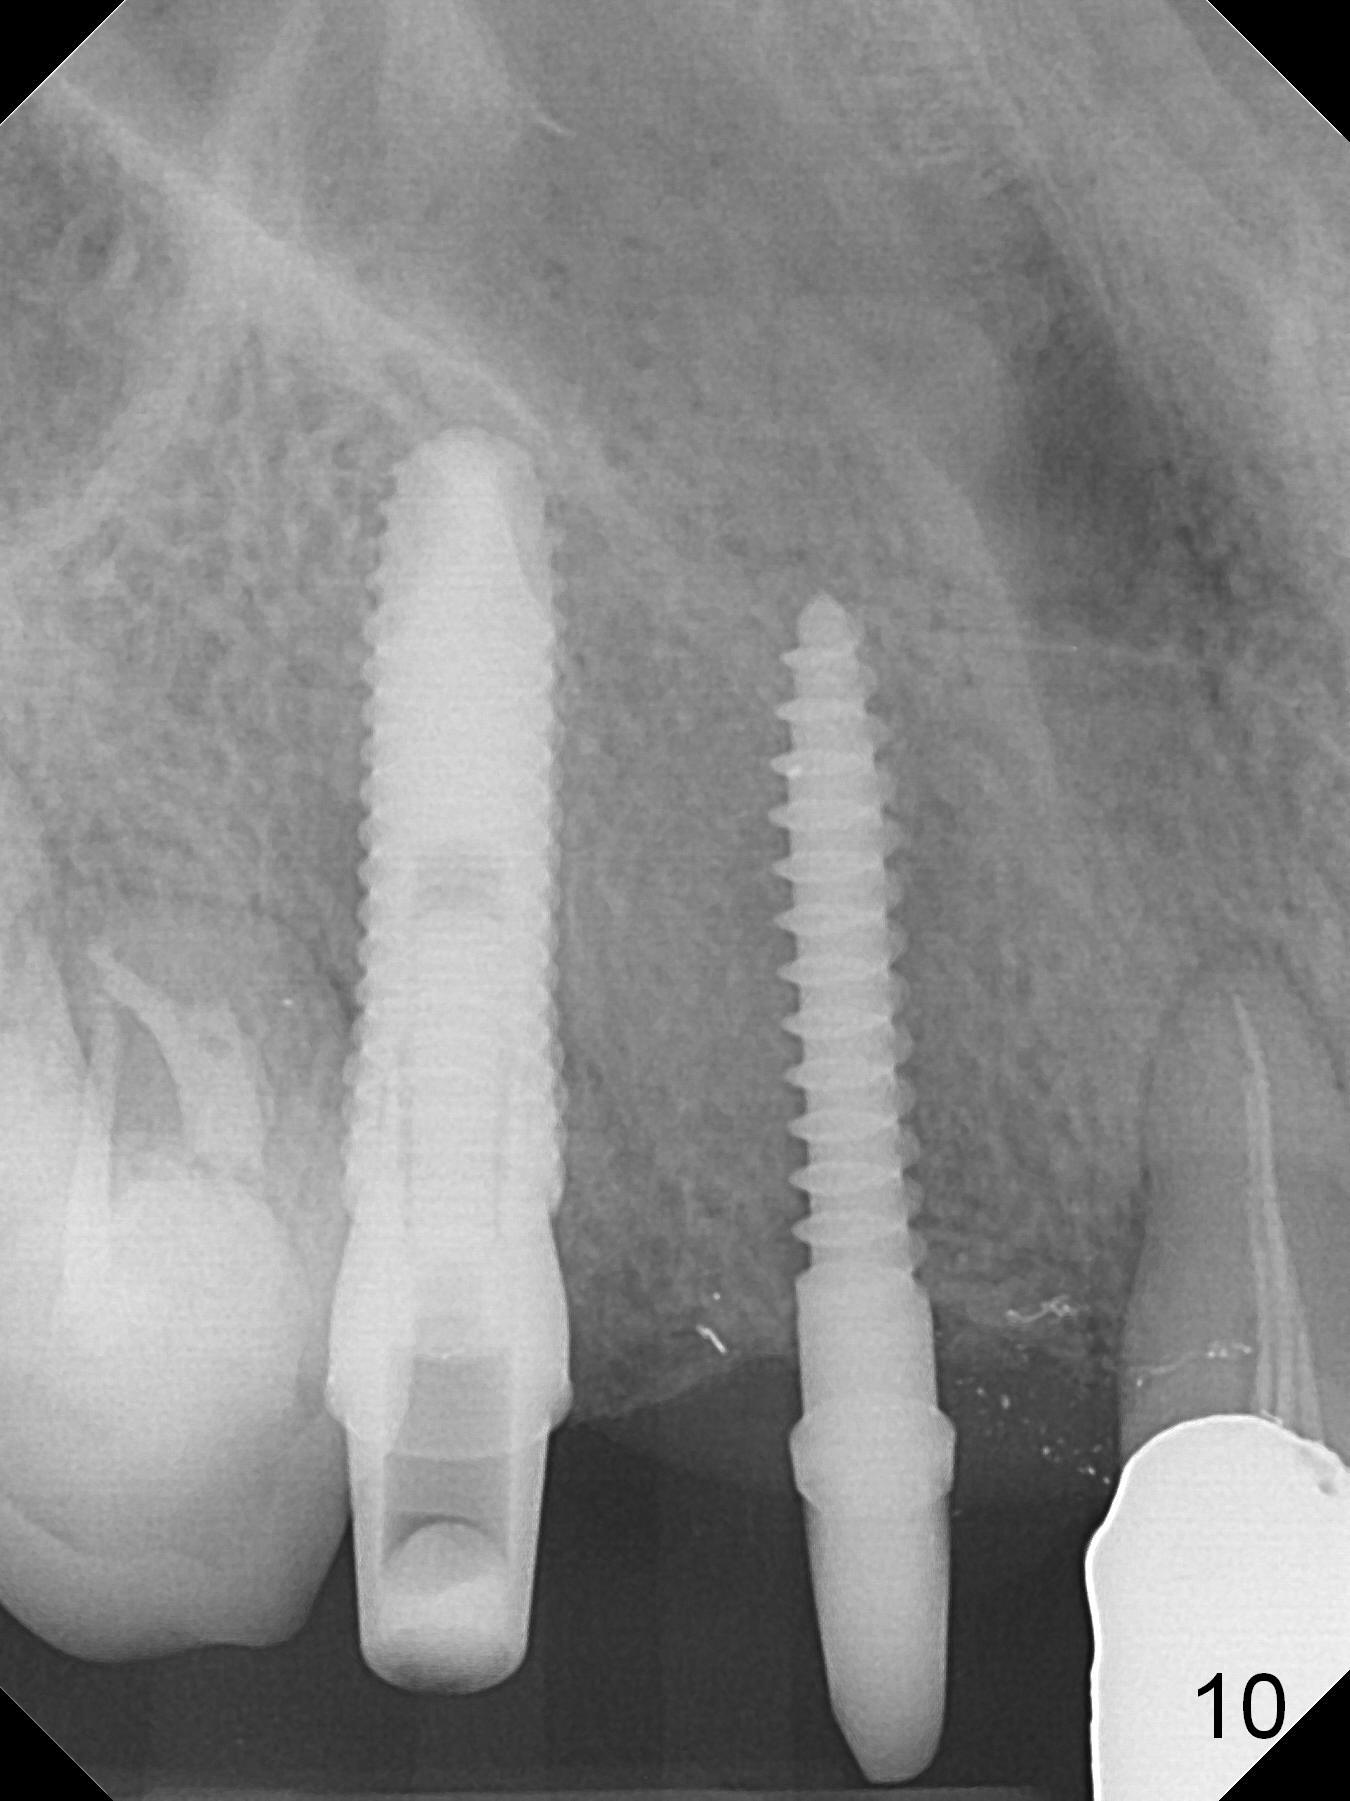

When the bridge is sectioned between #7 and 8, the tooth #6 is found non-salvageable (Fig.1).  Incision shows the atrophic buccal plate at #7 (Fig.2 arrowheads); to prevent the same feature from happening at #6 with thin buccal plate, the most buccal portion of the root is preserved (socket shield (Fig.2-4: *)).  The initial osteotomy is established in the palatal slope at #6 (Fig.5 circle) with 1.5 mm drill (Fig.6,7).  A portion of the root is visible in Fig.6 (arrowheads).  After sequential osteotomy with 2 mm, 3 mm (Fig.8) and 3.2 mm drills, a 4x15 mm implant is placed (Fig.10).  To accommodate the cross bite, the coronal portion of the implant (Fig.9 white circle) is positioned close to the socket shield.  It appears that the shield prevents the implant from encroaching the buccal plate.

Since the ridge at #7 is ~ 4 mm, a 2.5x14 mm 1-piece implant is placed (Fig.8) after 1.2 mm (Fig.7), and 1.5 mm drills at 12 mm and 2 mm drill at 8 mm.  Later the implant is placed deeper (Fig.10).  There is no bone loss 7 or 12 months postop, respectively (Fig.11,12).  After Diode gingivectomy, there is papillary formation (Fig.13).  No provisional is provided after impression (with the abutment torqued at #6) for oral hygiene.  With access holes at #6 and 7, crowns are bonded with minimal residual cement (Fig.14 <, which is removed later).  There is no hard (Fig.15,16) or soft (Fig.17 *) atrophy 26 months postop, i.e., 13 months post cementation, due to the presence of socket shield (Fig.15 <, as compared to Fig.1).  In fact the tooth #8 has mobility and fremitus (short root/poor crown/root ratio, Fig.16); occlusal adjustment is done 13 months post cementation.  The crown is dislodged 2 years 1 month post cementation; a prefabricated post is being tried in (Fig.18).  There is no atrophy, bone loss or infection at #6 (with socket sheath (*)) or 7 two years 5 months post cementation (Fig.20-27).